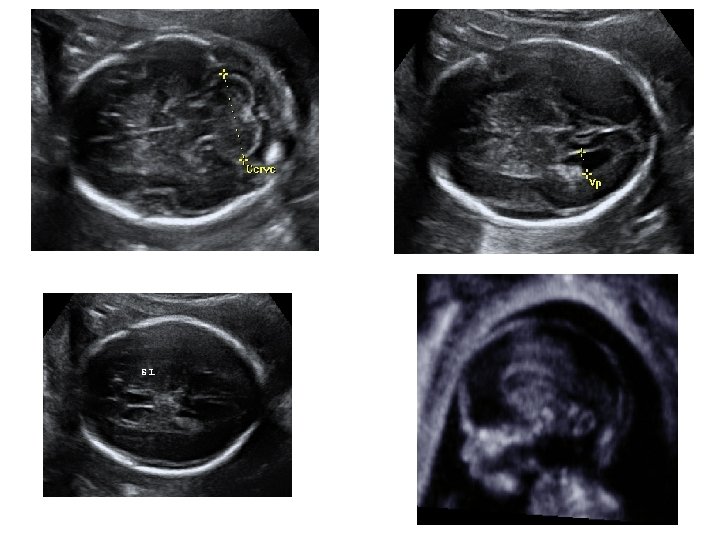

Échographie du 1 er trimestre • Entre 11 et 14 SA • Étudier la vitalité de l’embryon • Dater le début de la grossesse - LCC : longueur cranio-caudale - BIP : diamètre bipariétal - DAT : diamètre abdominale transverse - LF : longueur fémorale Ces mesures, à ce terme de la grossesse, donnent le terme avec une précision de ± 5 jours

• Étude morphologique succincte : - pôle céphalique : structures cérébrales symétriques, voûte crânienne présente - membres : 4 x 3 segments - estomac : présent - vessie : présente - axe rachidien, insertion cordonale • Annexes : - trophoblaste - quantité de liquide • Ovaires

Échographie du 2ème trimestre • Entre 21 et 23 SA • Évaluer la croissance fœtale - pôle céphalique BIP : diamètre bipariétal PC : périmètre céphalique - abdomen fœtal CA : circonférence abdominale - extrémités : LF : longueur fémorale

• Étude morphologique approfondie - pôle céphalique : contours de la boite crânienne, volume des ventricules latéraux, structures de la ligne médiane, cervelet (aspect et mesure de sa largeur) - distance inter-orbitaire - coupe nez-lèvre - profil : menton aligné avec le front, mesure des OPN

- thorax : cœur (position, 4 cavités équilibrées, septum inter ventriculaire, croisement Ao/AP), poumons - abdomen : paroi intègre, estomac (position, volume), vésicule biliaire, intestin grêle - arbre urinaire : vessie (position, volume), 2 reins - sexe - rachis avec son revêtement cutané - membres : 4 x 3 segments, 5 doigts aux 2 mains, mouvements d’ouverture des mains, mesure du pied